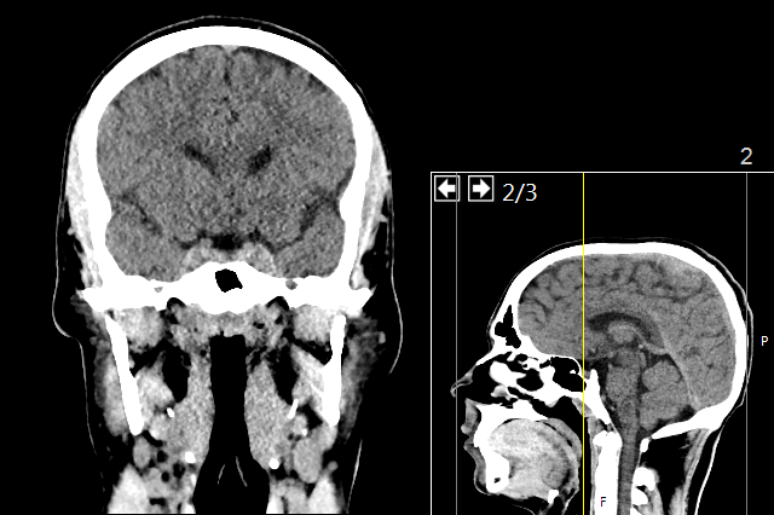

Cérebro tende a guardar memórias emocionais com mais facilidade

Foto: Mikael Häggström, M.D. Author info - Reusing images- Conflicts of interest:  NoneMikael Häggström, M.D.Consent note: Written informed consent was obtained from the individual, including online publication., CC0, via Wikimedia Commons